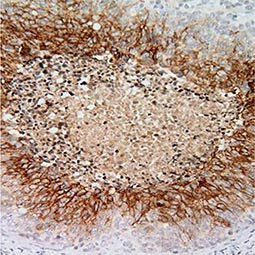

Fig. 2. Genes that are regulated by HIF-1α

Genes regulated by HIF-1α (Fig. 2) are important for tumor metabolism, proliferation, survival, angiogenesis, and metastasis. Therefore, inhibition of HIF-1α and its related proteins has become a promising direction for anticancer therapy research.

As oxygen supply in a tumor is frequently suboptimal, cancer cells often increase the expression of HIF-1α to stimulate gene expression that allows them to survive, proliferate, invade surrounding tissue, and metastasize to distant sites. In addition, the hypoxic tumor milieu can make cancer cells less sensitive to chemotherapy and radiotherapy.